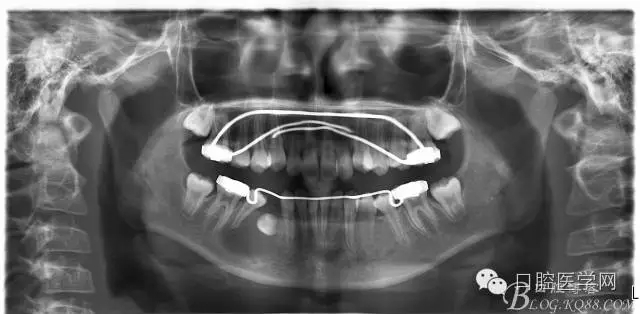

1:SWA.

2:拔牙矯治,拔出4顆第一前磨牙。

3:上下頜利用拔牙間隙解除擁擠并內(nèi)收上下前牙,改善唇側(cè)貌。

4:導(dǎo)下頜向前改善頜面?zhèn)让病?/p>

5:上頜TPA+NanceArch強(qiáng)支抗.

6:下頜囊腫開(kāi)窗引流,雙側(cè)第一恒磨牙舌桿保持牙位。擇期拔除第一前磨牙。